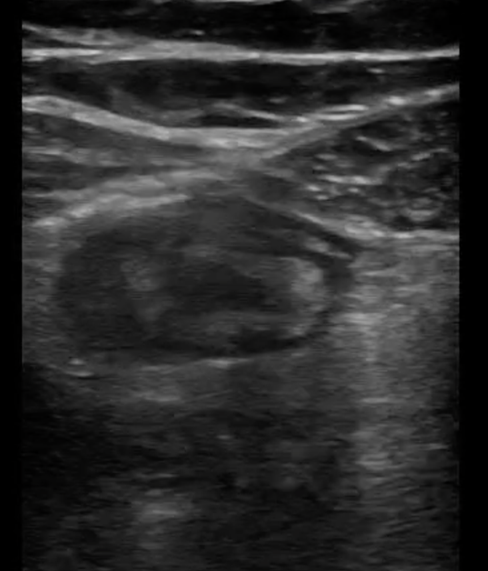

The appendix is most reliably found in the right lower quadrant; the base extends from the proximal cecum and lies anterior to the psoas muscle and the right iliac vessels. Most of the time the distal tip is retrocecal, though the challenge in localization is augmented as the appendix can be pelvically oriented (Images 5 and 6) or directed elsewhere in the abdomen. The normal appendix is tubular, non-peristalsing, compressible, and blind-ended, measuring less than 6 mm. (Image 7)

Image 5. Normal appendix

Image 6. Normal appendix (Yellow: Appendix, Red: Iliac Artery, Blue: Iliac Vein)